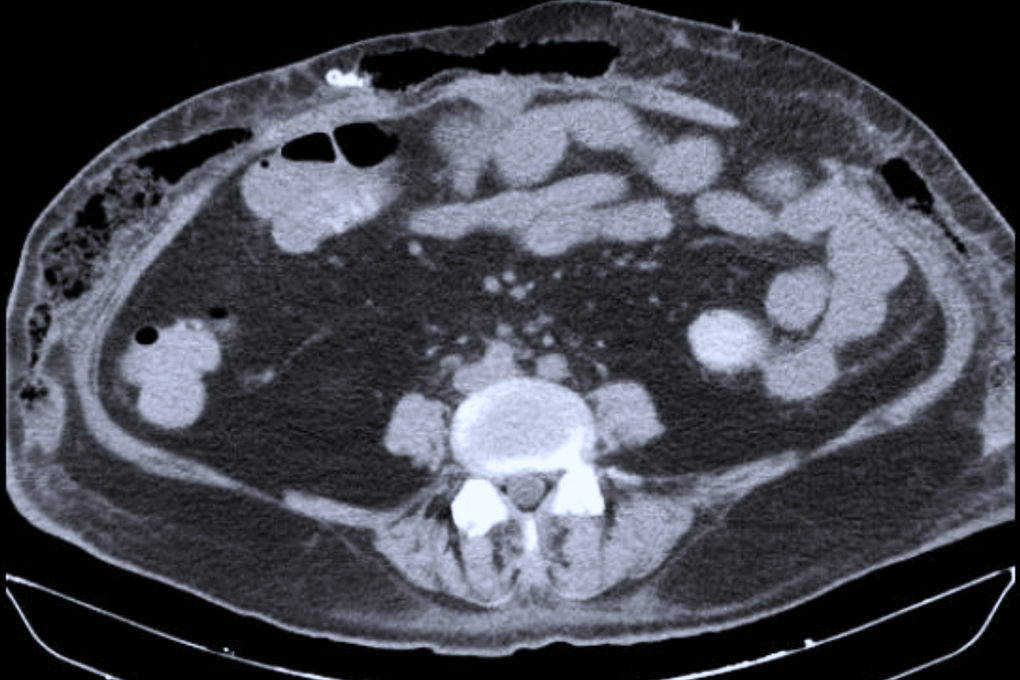

Ngày 4/12, Bệnh viện Chợ Rẫy cho biết, người được phẫu thuật là ông N.T.P. (57 tuổi, ngụ tỉnh Khánh Hòa), bị u tuyến yên khổng lồ và thị lực suy giảm nghiêm trọng.Chia sẻ cùng bác sĩ điều trị, bệnh nhân cho biết trước đó đã đi khám và điều trị nhiều nơi suốt 10 năm vì mờ mắt kéo dài, nhưng không phát hiện được nguyên nhân từ hệ thần kinh.Đến ngày 10/11, bệnh nhân được chuyển vào Bệnh viện Chợ Rẫy trong tình trạng đau nhức đầu nhiều, suy tuyến yên và thị lực rất yếu, chỉ còn phân biệt được bóng b...